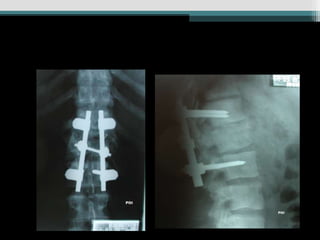

Caso 3 (24anos, queda Fk e)